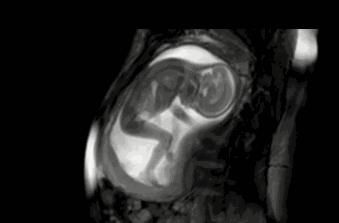

等到他再大点的时候,“蛙泳”项目已经无法进行了,但是你以为他长大点了就会听话、懂事,当个乖宝宝吗?

可不会。

咦?这地儿怎么越来越小了,不管,我挤,我顶......

▼

顶了这么久,“房子”怎么还是这么小?

管他呢,我要出去,我要游泳,我继续蹬腿,我蹬……

哇,看到没有!我的大长腿是不是很迷人!